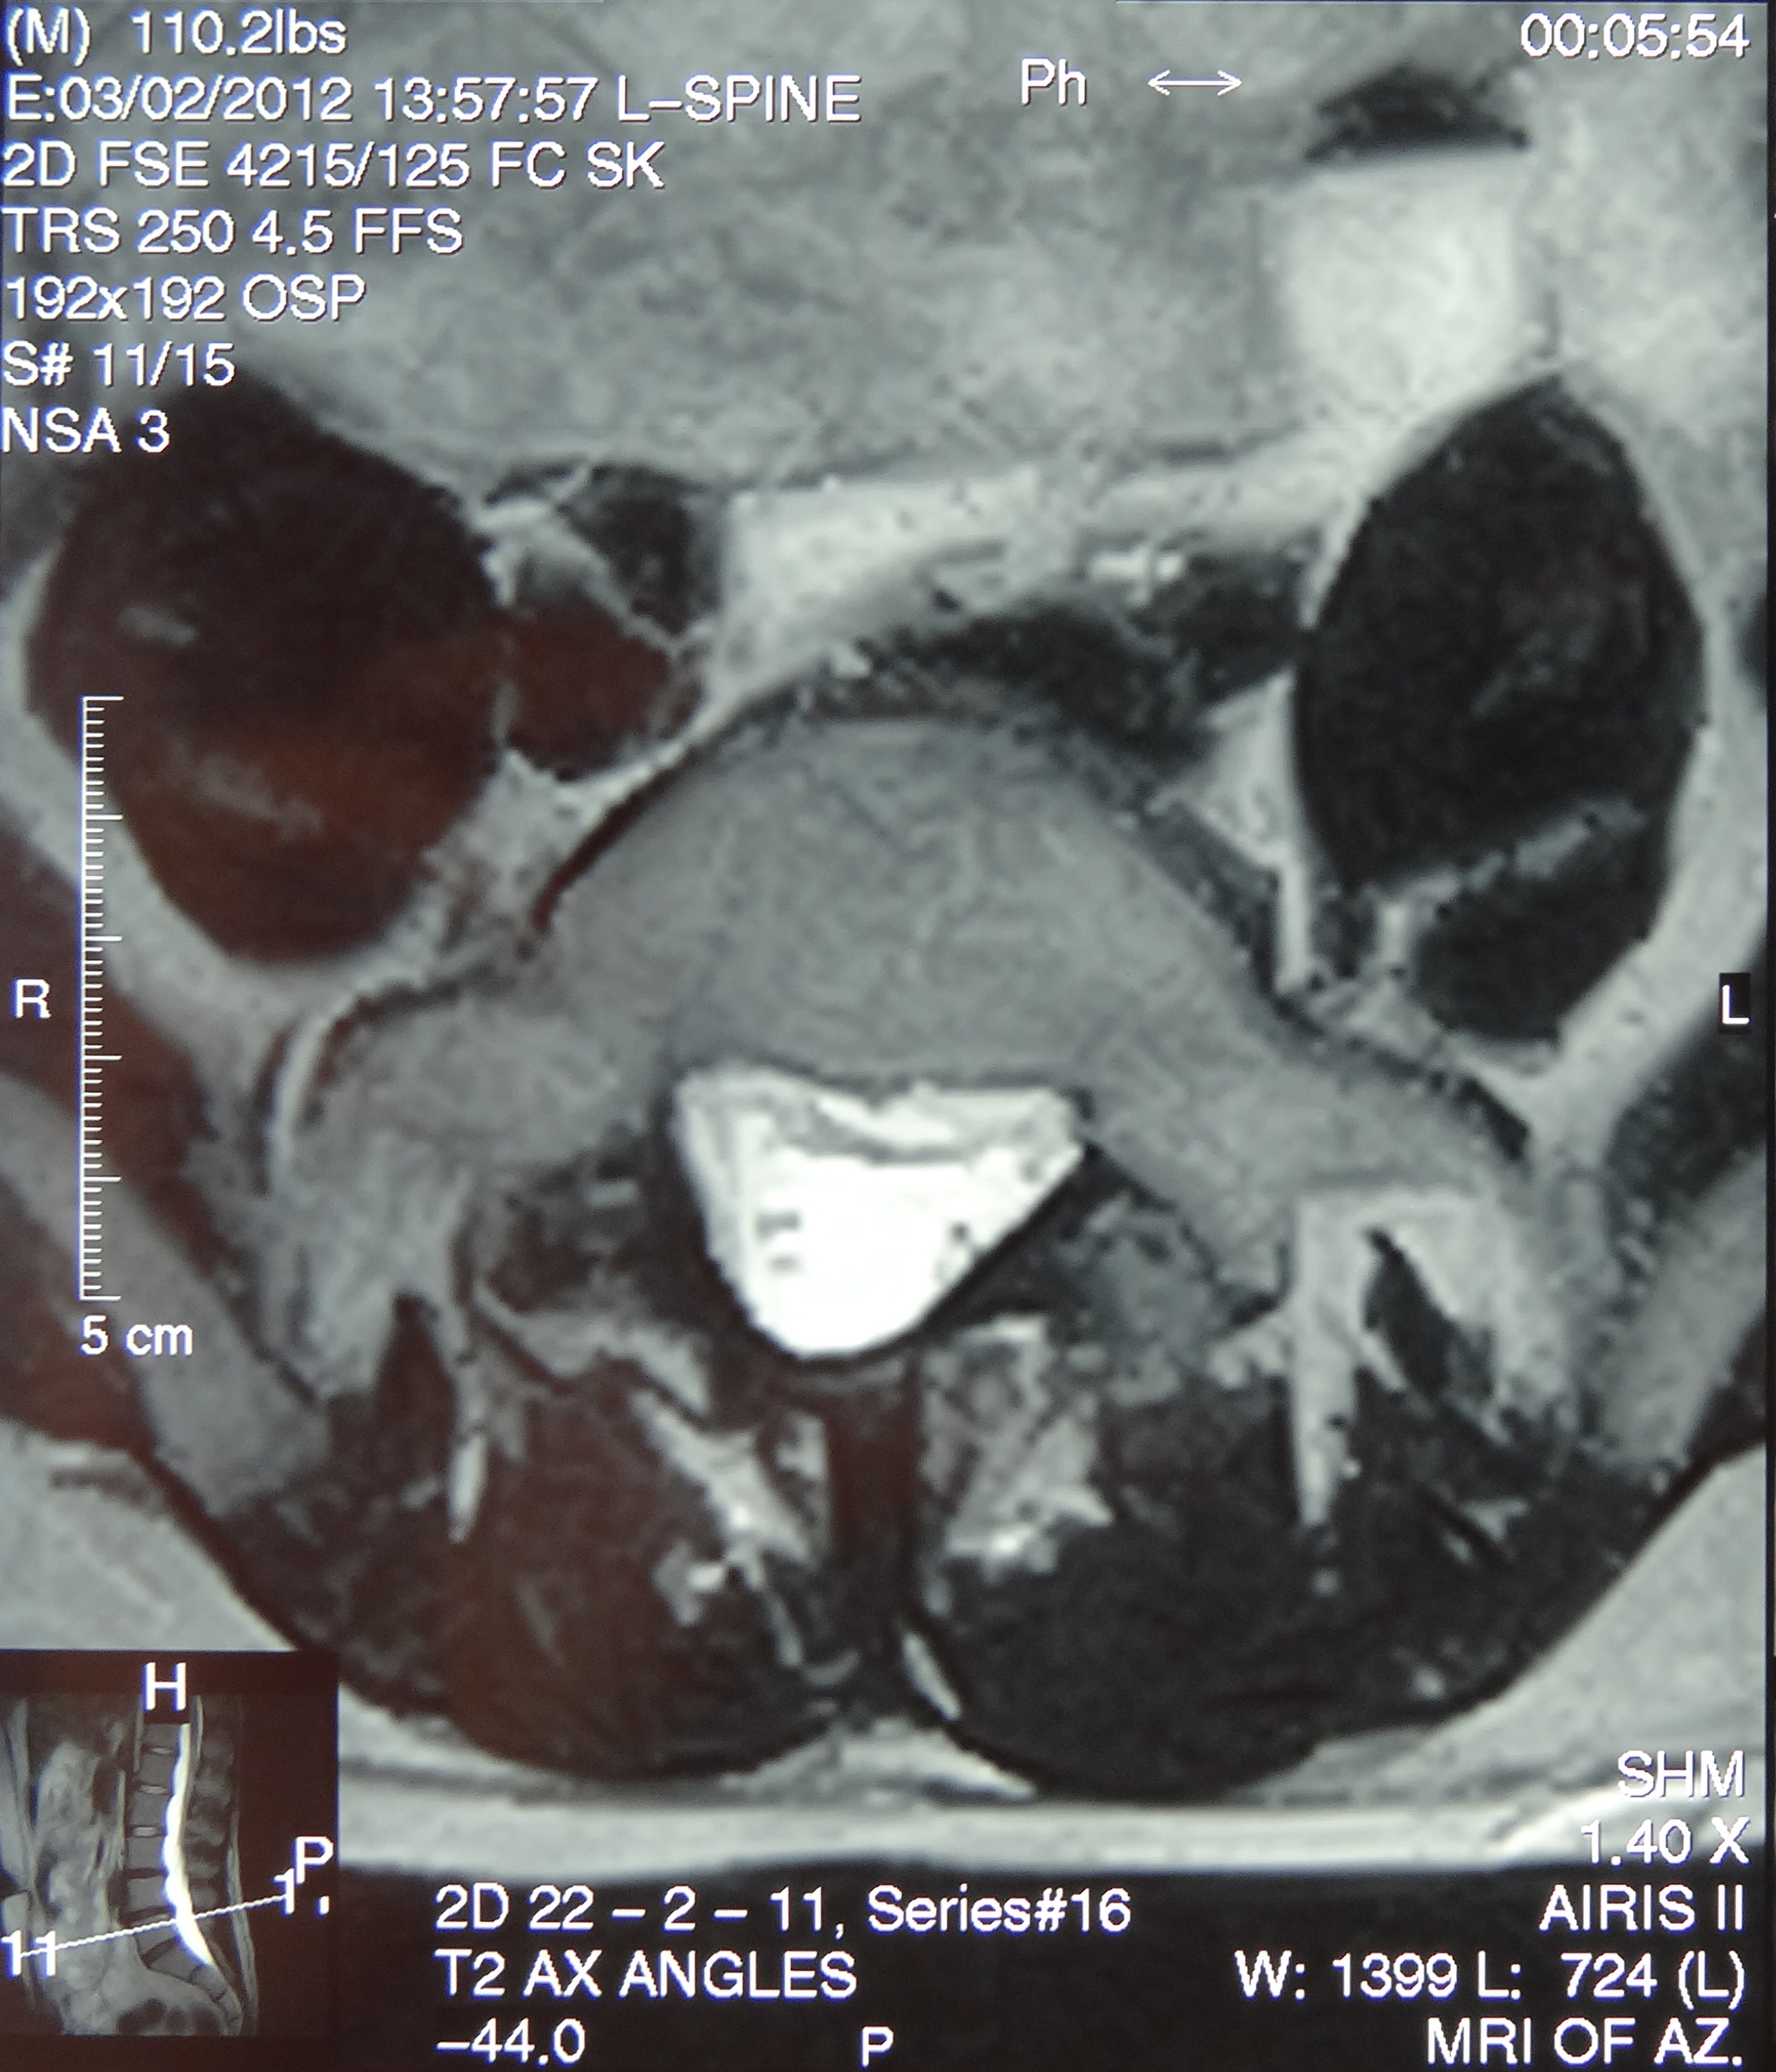

December 2019 MRI

IMPRESSION

- Medial: Nondisplaced horizontal longitudinal tear extending obliquely to the

undersurface of the meniscal body and posterior horn segments. No chondral erosion or thinning. Intact root ligaments. - Intact anterior cruciate ligament. Normal posterior cruciate ligament. Intact medial

lateral supporting structures. - No joint effusion or synovitis. No periarticular muscle injury. No osseous contusion

or stress injury. Minimal fluid in the semimembranosus-medial gastrocnemius bursa. No

frank Baker's cyst.

June 2020 MRI

- Healed femoral-sided ACL tear with partial attenuation of the proximal ACL fibers.

- Progressive healing of horizontal oblique tear of the medial meniscus posterior horn.

- Chronic inferiorly displaced meniscal flap tear at the lateral meniscus posterior

horn-root junction, less conspicuous than on prior MR imaging. Resolution of previously

noted horizontal longitudinal tear of the body-posterior horn segments. - No new evidence of internal derangement. No acute osseous abnormality.